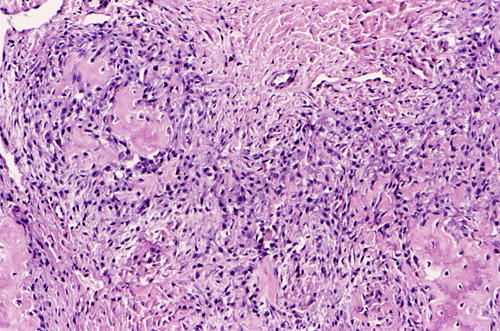

Pathology of the case:  An incisional biopsy yielded several small fragments of gritty, tan to translucent tissue. The histopathology varies in different parts of the tumor. In some areas, the lesion is composed predominantly of islands of neoplastic cartilage with focal osteoid formation and rimmed by spindle cells (Panel E). In other areas, densely packed spindle cells proliferation admixed with hypocellular fibrous tissues is present (Panel F). On high magnification, the spindle cells appear to be pleomorphic and hyperchromatic (Panel G). Mitotic figures are present but not numerous. No atypical mitoses are noted. Small foci of osteoid are best appreciated at higher magnification ("OS" in Panel G). It appears that this tumor has arisen from the medullary cavity and is best classified as a central osteosarcoma.

Osteosarcoma is a malignant tumor characterized by direct formation of bone or osteoid by the proliferating neoplastic cell. Other than sharing this characteristic, osteosarcoma is one of the most heterogeneous tumor from the histopathologic perspective.  The histologic features vary from different areas of the same tumor and among different tumors. In general, several major patterns are recognized: osteoblastic, chondroblastic, fibroblastic, giant-cell rich, small cell, telangiectatic,  and others. The amount of osteoid and ossified tissue can vary tremendously and it is not uncommon that it can only be found after careful search. The osteoid can form well-defined structures that mimic trabecular bone or as irregular deposits. The current trend is to classify osteosarcomas into low- and high-grade tumors. It is the histologic grade rather than tissue pattern that has greatest bearing on prognosis.

Similar to osteosarcomas arising from the flat bones and ribs (e.g., osteosarcomas of the pelvic bones), about 30% of the osteosarcomas of the jaws are chondroblastic type and contain a substantial amount of cartilage. Lobules of neoplastic cartilage may dominate the histologic picture in some cases and osteoid production by the neoplastic cells may occur only focally.  The cartilaginous differentiation can be heterogeneous and represent all stages of cartilaginous matrix formation. Stigmata of malignancies including nuclear pleomorphism, mitosis, atypical mitotic figures, and necrosis can all be seen in osteosarcomas.